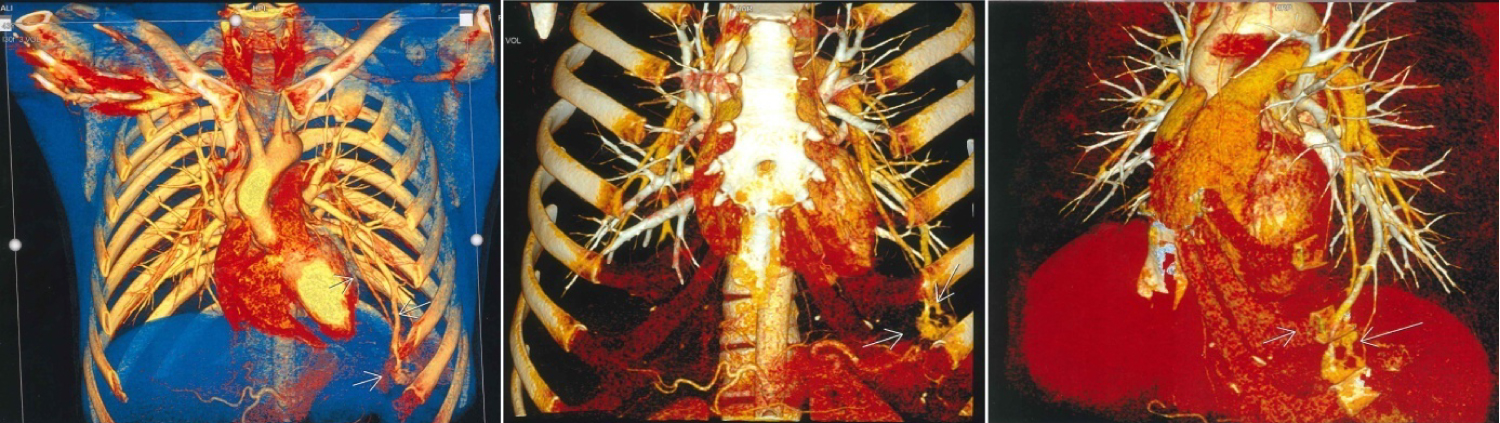

The chest CT scan did not reveal any lesional process, but did show a varicose appearance involving the antero-basal segment of the left lower lobe of vascular type, causing the pulmonary vein to communicate distally with the pulmonary artery (Figure 1). A thoracic angioscan with arterial and venous time, and a three-dimensional reconstruction was performed, confirmed the diagnosis of MAVP, showing an abnormally dilated aspect of the left lower lobe pulmonary vein, measured at 5 mm, who's followed to its distality leads to a sacciform formation, extended over 17 mm, with venous return, measured at 2.5 mm and communicating with the lower lobar of the left pulmonary artery (Figure 2).

Figure 2: Three-dimensional reconstruction of the frontal angioscanner of the arteriovenous malformation of the antero-basal seat of the left lower lobe (arrows). View Figure 2